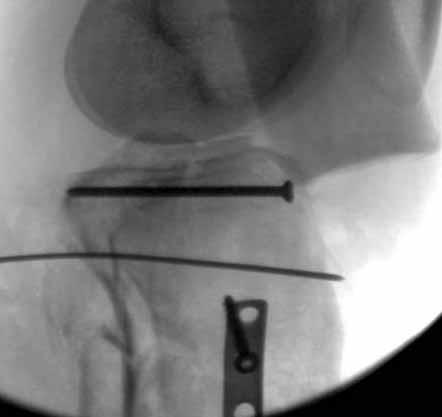

Двухколоннный перелом тибиал плато с вовлечением проксимального диафиза. Внутрисуставной компонент без смещения, и такой перелом можно лечить любым из описанных методов, о которых говорят наши коллеги.

Удобно аппаратом Илизарова или интрамедуллярным гвоздем. Гвозди не так сложно, как пугают, тем более Александр готов помощь с методичкой. Сперва надо установить компрессирующие шурупы на мыщелки. Давно отказались в пользу 3.5-4.0 мм кортикальных вместо толстых спонгиозных, потому что не доказаны преимущества толстых шурупов. Тонкие шурупы в субхондральной зоне смотрятся намного элегантнее, чем толстые 6.5.

Это мероприятие превращает перелом в простой диафизарный, который легко можно фиксировать гвоздем. Шурупы надо установить сзади предполагаемого места введения гвоздя.